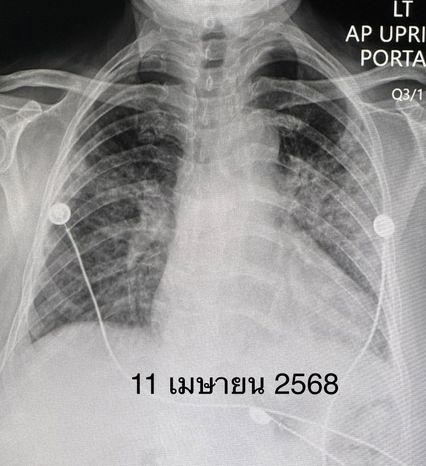

วินิจฉัยว่า ผู้ป่วยรายนี้เป็นโรคภูมิต้านทานตัวเองชนิด Anti-MDA5 antibody positive dermatomyositis ทำให้เนื้อเยื่อปอดอักเสบ และปอดเกิดพังผืดอย่างรวดเร็ว ไม่มีกล้ามเนื้ออ่อนแรง ไม่มีความผิดปกติของผิวหนังให้ยาสเตียรอยด์ชนิดฉีดขนาดสูง ต่อมาเปลี่ยนเป็นชนิดกิน ยากดภูมิคุ้มกันไมโคฟีโนเลต (mycophenolate) ยาไฮดรอกซีคลอโรควิน (hydroxychloroquine) และยา Tolvaptan รักษาโรคโซเดียมในเลือดต่ำ

หลังได้รับยา คนไข้เหนื่อยน้อยลง ระดับออกซิเจนที่ปลายนิ้วดีขึ้น ใช้ออกซิเจนแบบหนวดกุ้งธรรมดาทางจมูก ไม่ต้องใช้ High-Flow nasal O2 cannula เอกซเรย์ปอดดีขึ้นช้า ๆ ลุกขึ้นเดินได้ ระดับโซเดียมในเลือดเกือบปกติ กลับบ้านได้หลังจากรักษาอยู่ในโรงพยาบาล 15 วัน หมอนัดติดตามเป็นคนไข้นอกต่อไป